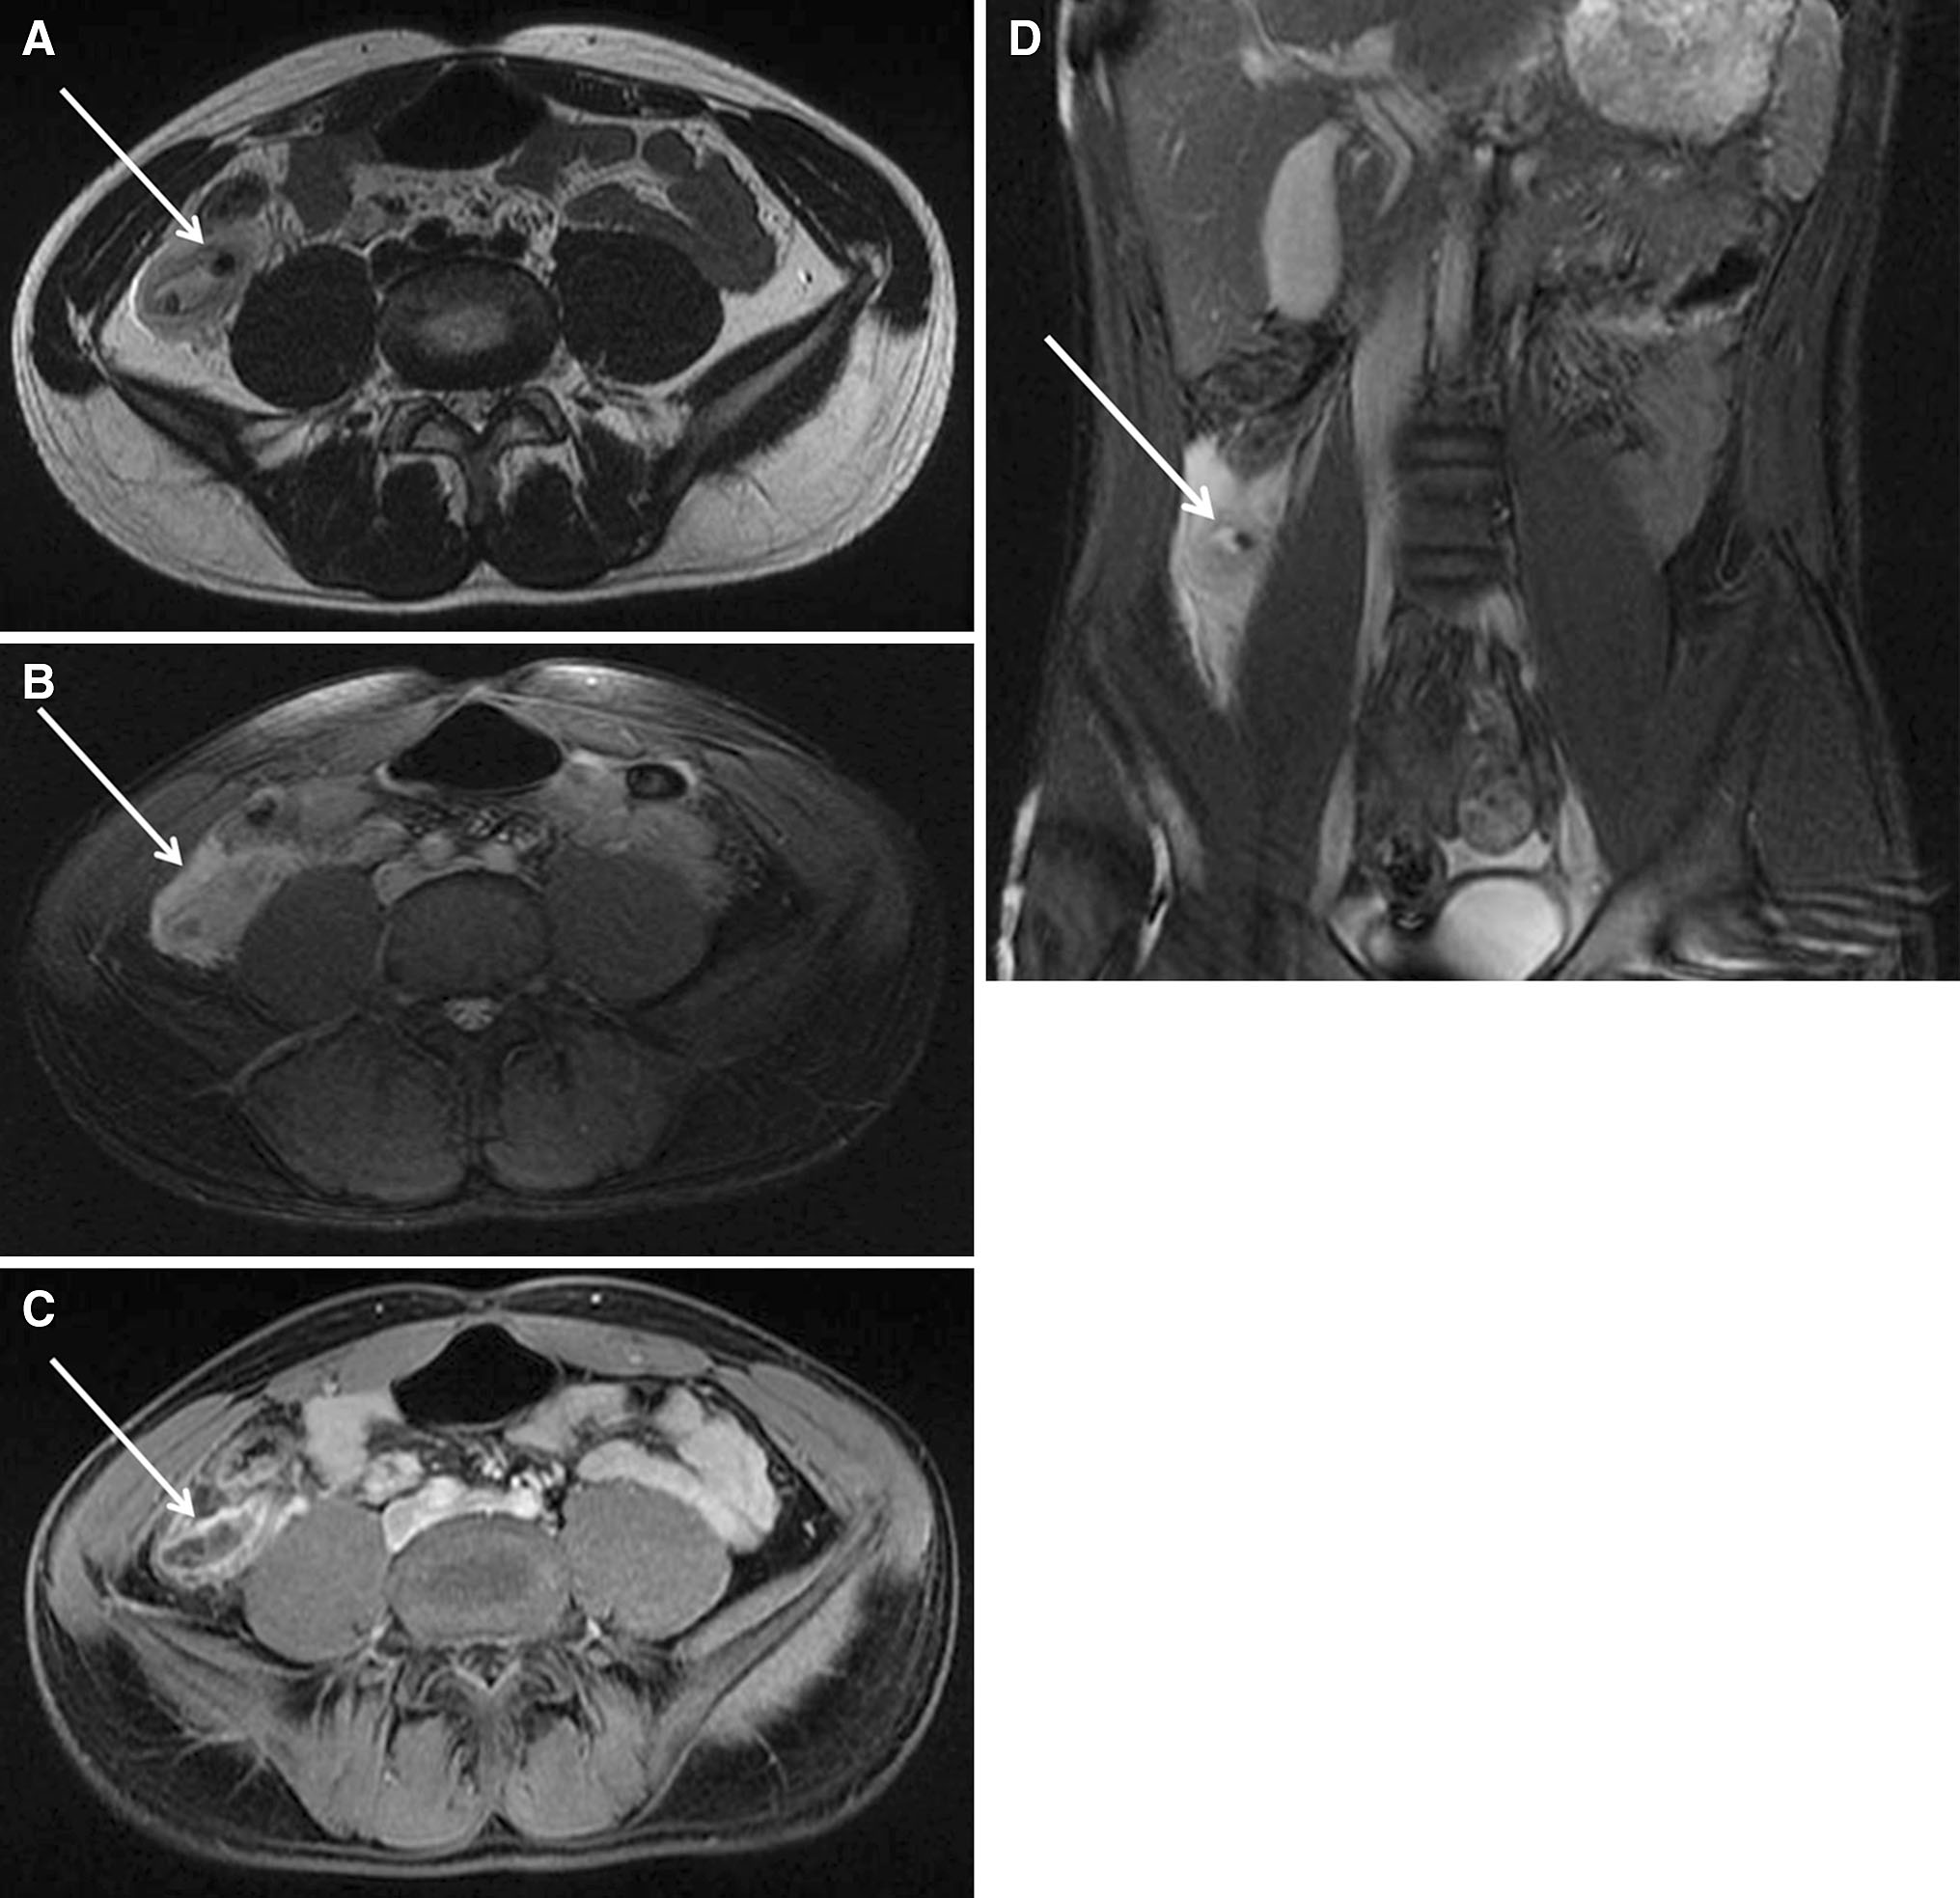

Sharp and Children's MRI Center (SCMRI) has continued their work eliminating harmful exposure of children to ionizing radiation by using MRI to diagnose acute appendicitis. Investigators there have shown in a recent publication in Abdominal Imaging that MRI is accurate in children with very early symptoms of abdominal pain. This is an extremely important finding as ultrasound, the main first-line imaging technology competing with MRI at children's hospitals across the nation, has been previously shown to be inaccurate for appendicitis in children with early symptoms of abdominal pain. This can potentially lead to delays in both diagnosis and treatment or even missed diagnoses, putting children's health at risk.

The new study concluded that contrast-enhanced MRI is capable of providing accurate diagnosis of acute appendicitis in children with early symptoms of abdominal pain. MRI is shown to be an effective substitute to CT and ultrasound and provides additional diagnostic information that they may not provide.